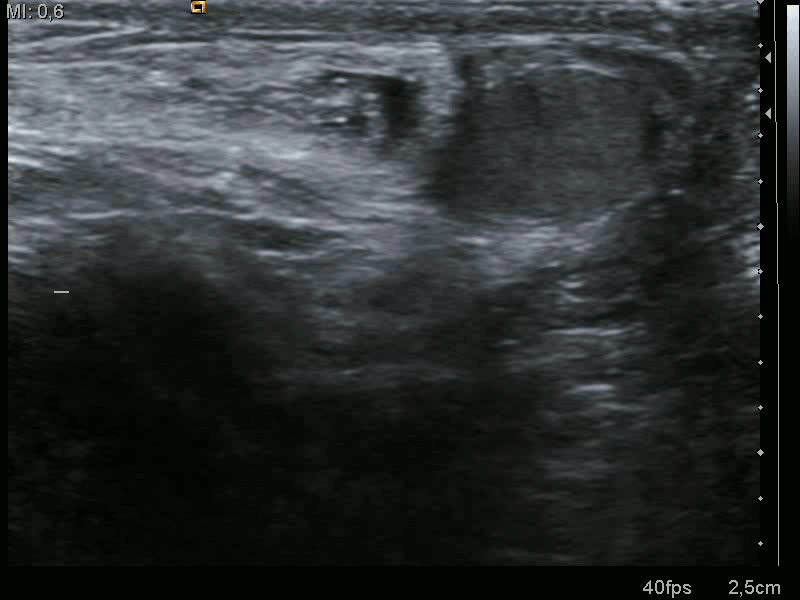

Как узнать, что это грыжа

Грыжа не появляется за один день. Сначала в канал выпирает внутренняя выстилка живота – брюшина. Постепенно туда проникает петля кишечника. Но она периодически выходит и выходит в грыжевые ворота. Если грыжа увеличивается и прогрессирует, все больший участок кишечника занимает не свое место. И в один прекрасный день он перестает возвращаться внутрь.

Увидеть грыжу можно при натуживании, достаточно задержать дыхание и сильно напрячься. А после расслабления выпячивание в паху исчезает. Со временем эта «забава» начнет сопровождаться дискомфортом, болью. В запущенной стадии урчит кишечник, мучает несварение и газы.